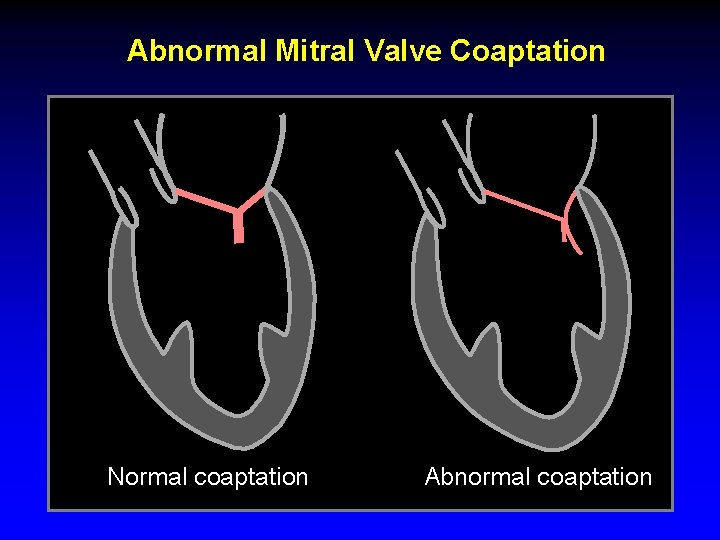

Abnormal Mitral Valve Coaptation Normal coaptation Abnormal coaptation